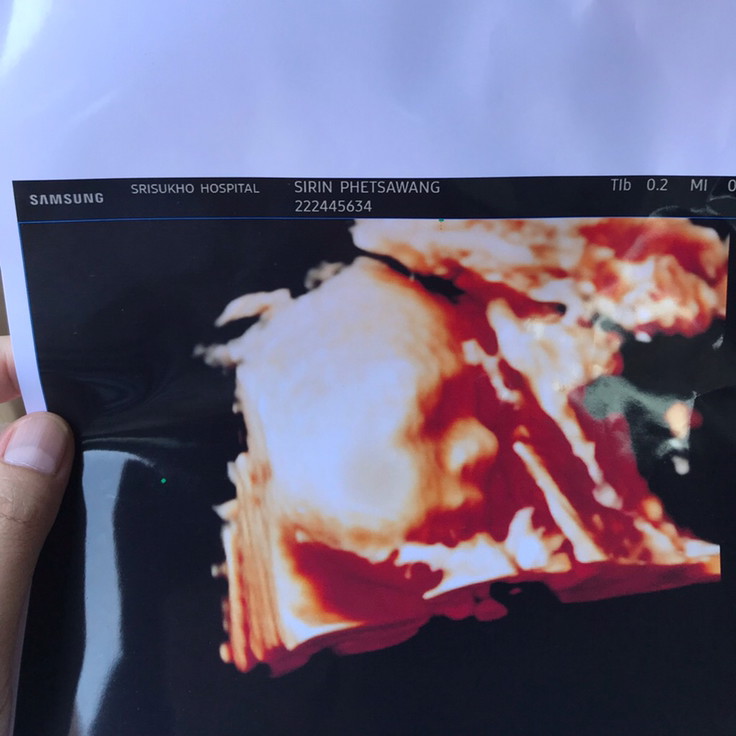

เอาเด็กชายปากคว่ำ เดือน พย. มาอวดจ้า

อายุครรถ์ 32วีค5วัน ผมหนัก 2,100 แล้วครับ ขอดูเด็กเดือน พย. น่ารักๆหน่อยครับ ผมไม่ชอบเลยเวลาคุณหมอซาวด์ หน้าจะบึ้งหน่อยๆ55555

คุณหมอบอกกลับหัวแล้วค่ะแม่